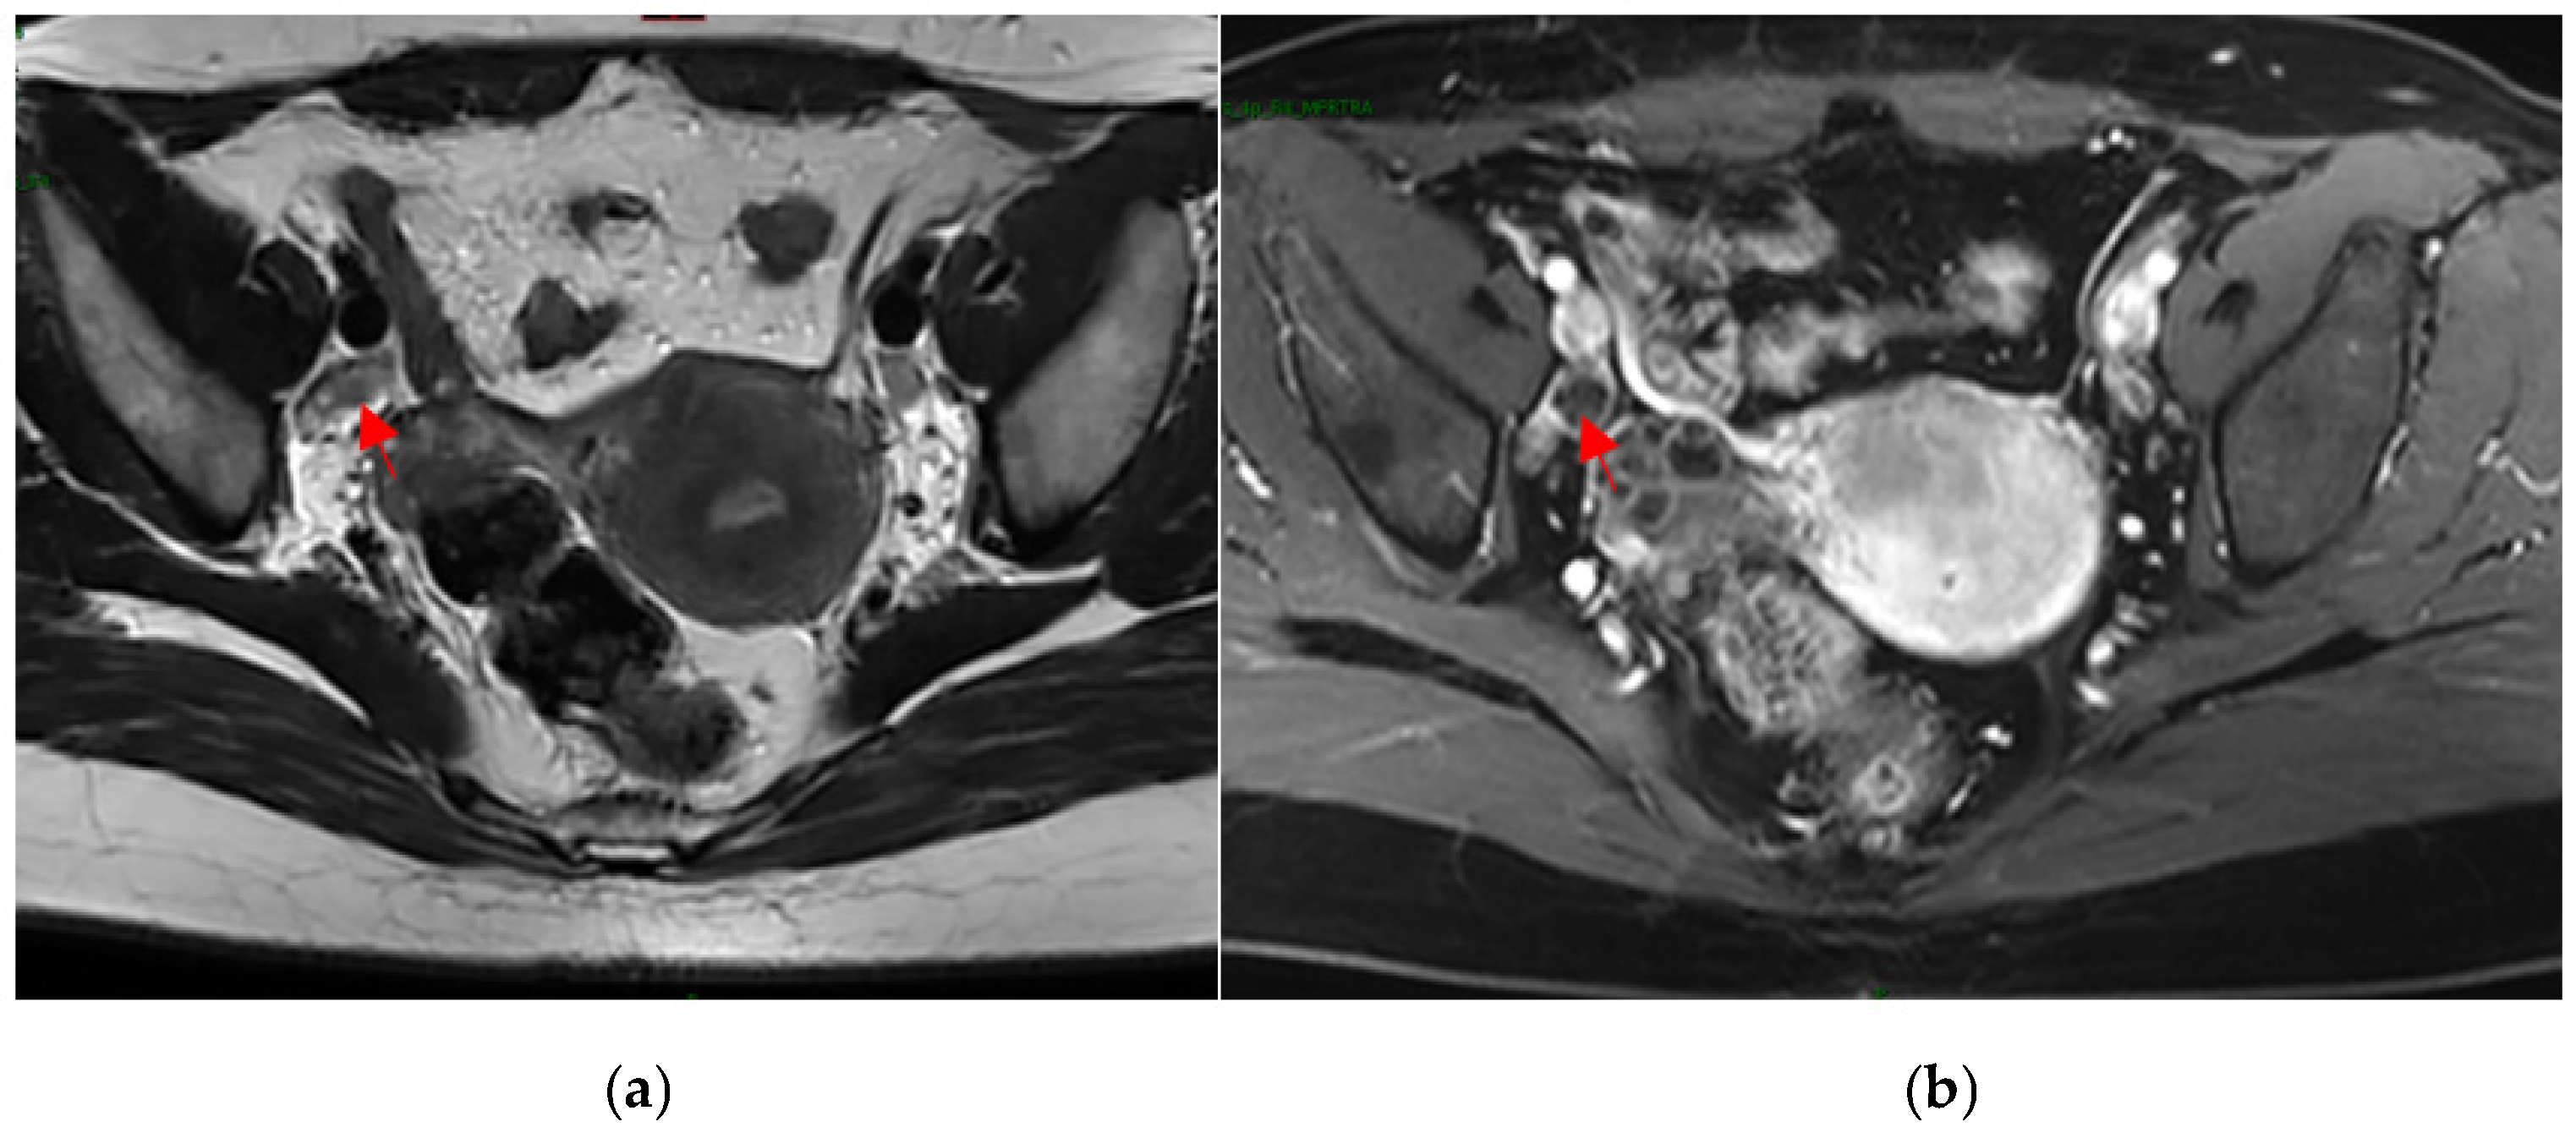

4.3. MRI Image-Processing Model